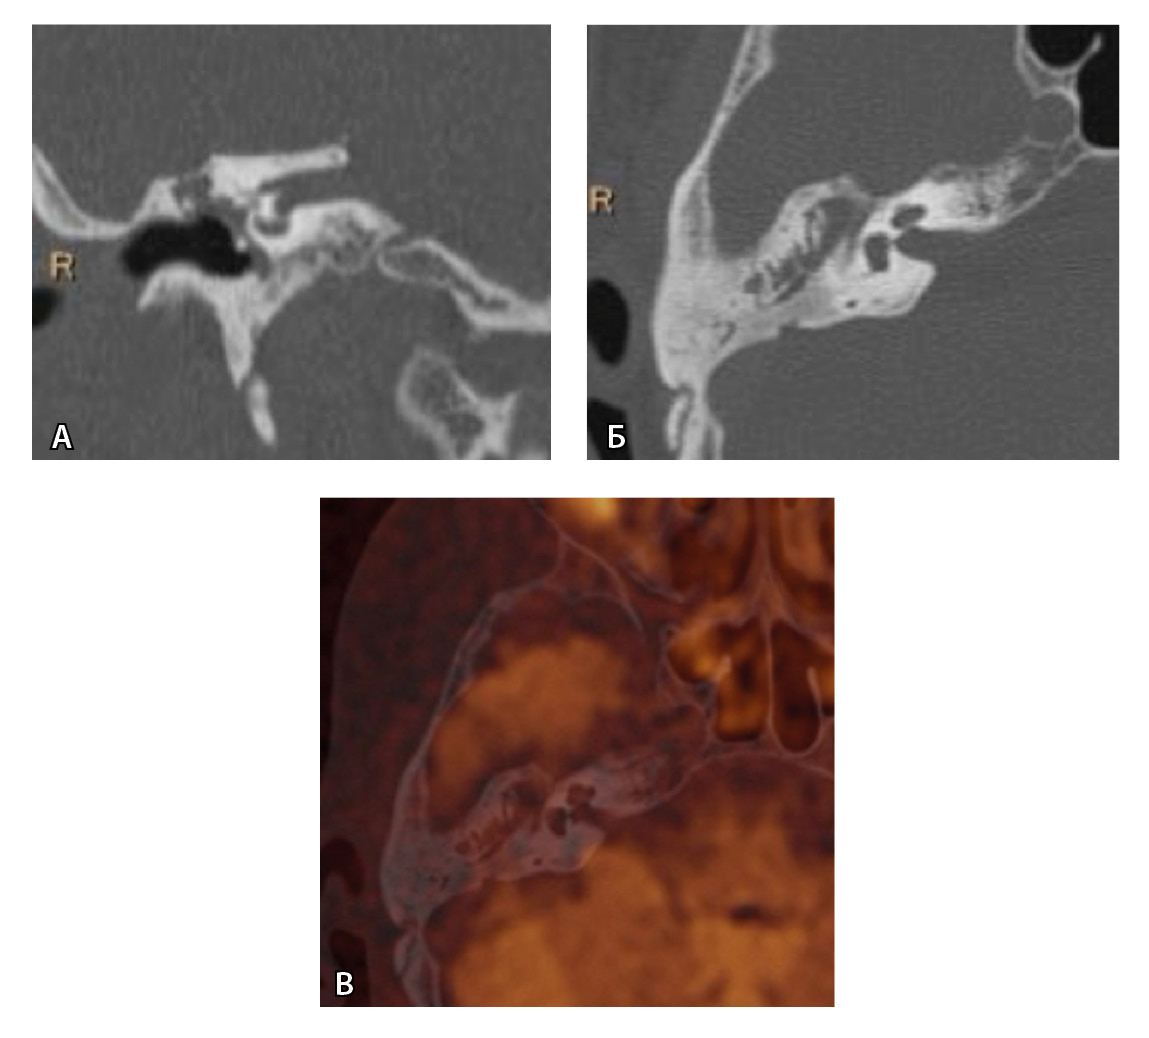

На рис. 3 и 4 показано расхождение данных КТ и МРТ.

Рис. 3. Хронический правосторонний средний отит. По данным компьютерной томографии (А, Б) нет ремоделирования барабанной полости, деструкции и смещения косточек, скутум сохранен, данных за холестеатому нет. При магнитно-резонансной томографии (В, Г) у того же пациента выявлен очаг высокого магнитно-резонансного сигнала, который при слиянии локализовался в области пространства Пруссака. Заключение и интраоперационно – холестеатома пространства Пруссака

Рис. 4. При компьютерной томографии (КТ) визуализируются признаки хронического гнойного среднего отита справа. Наблюдаются латерализация косточек среднего уха и узурация их по имедиальной поверхности на уровне эпитимпанума (тело наковальни и головка молоточка) – классические КТ-признаки холестеатомы натянутой части барабанной перепонки (А, Б). Однако по данным магнитно-резонансной томографии (В) и в последующем при оперативном лечении холестеатома не подтверждена